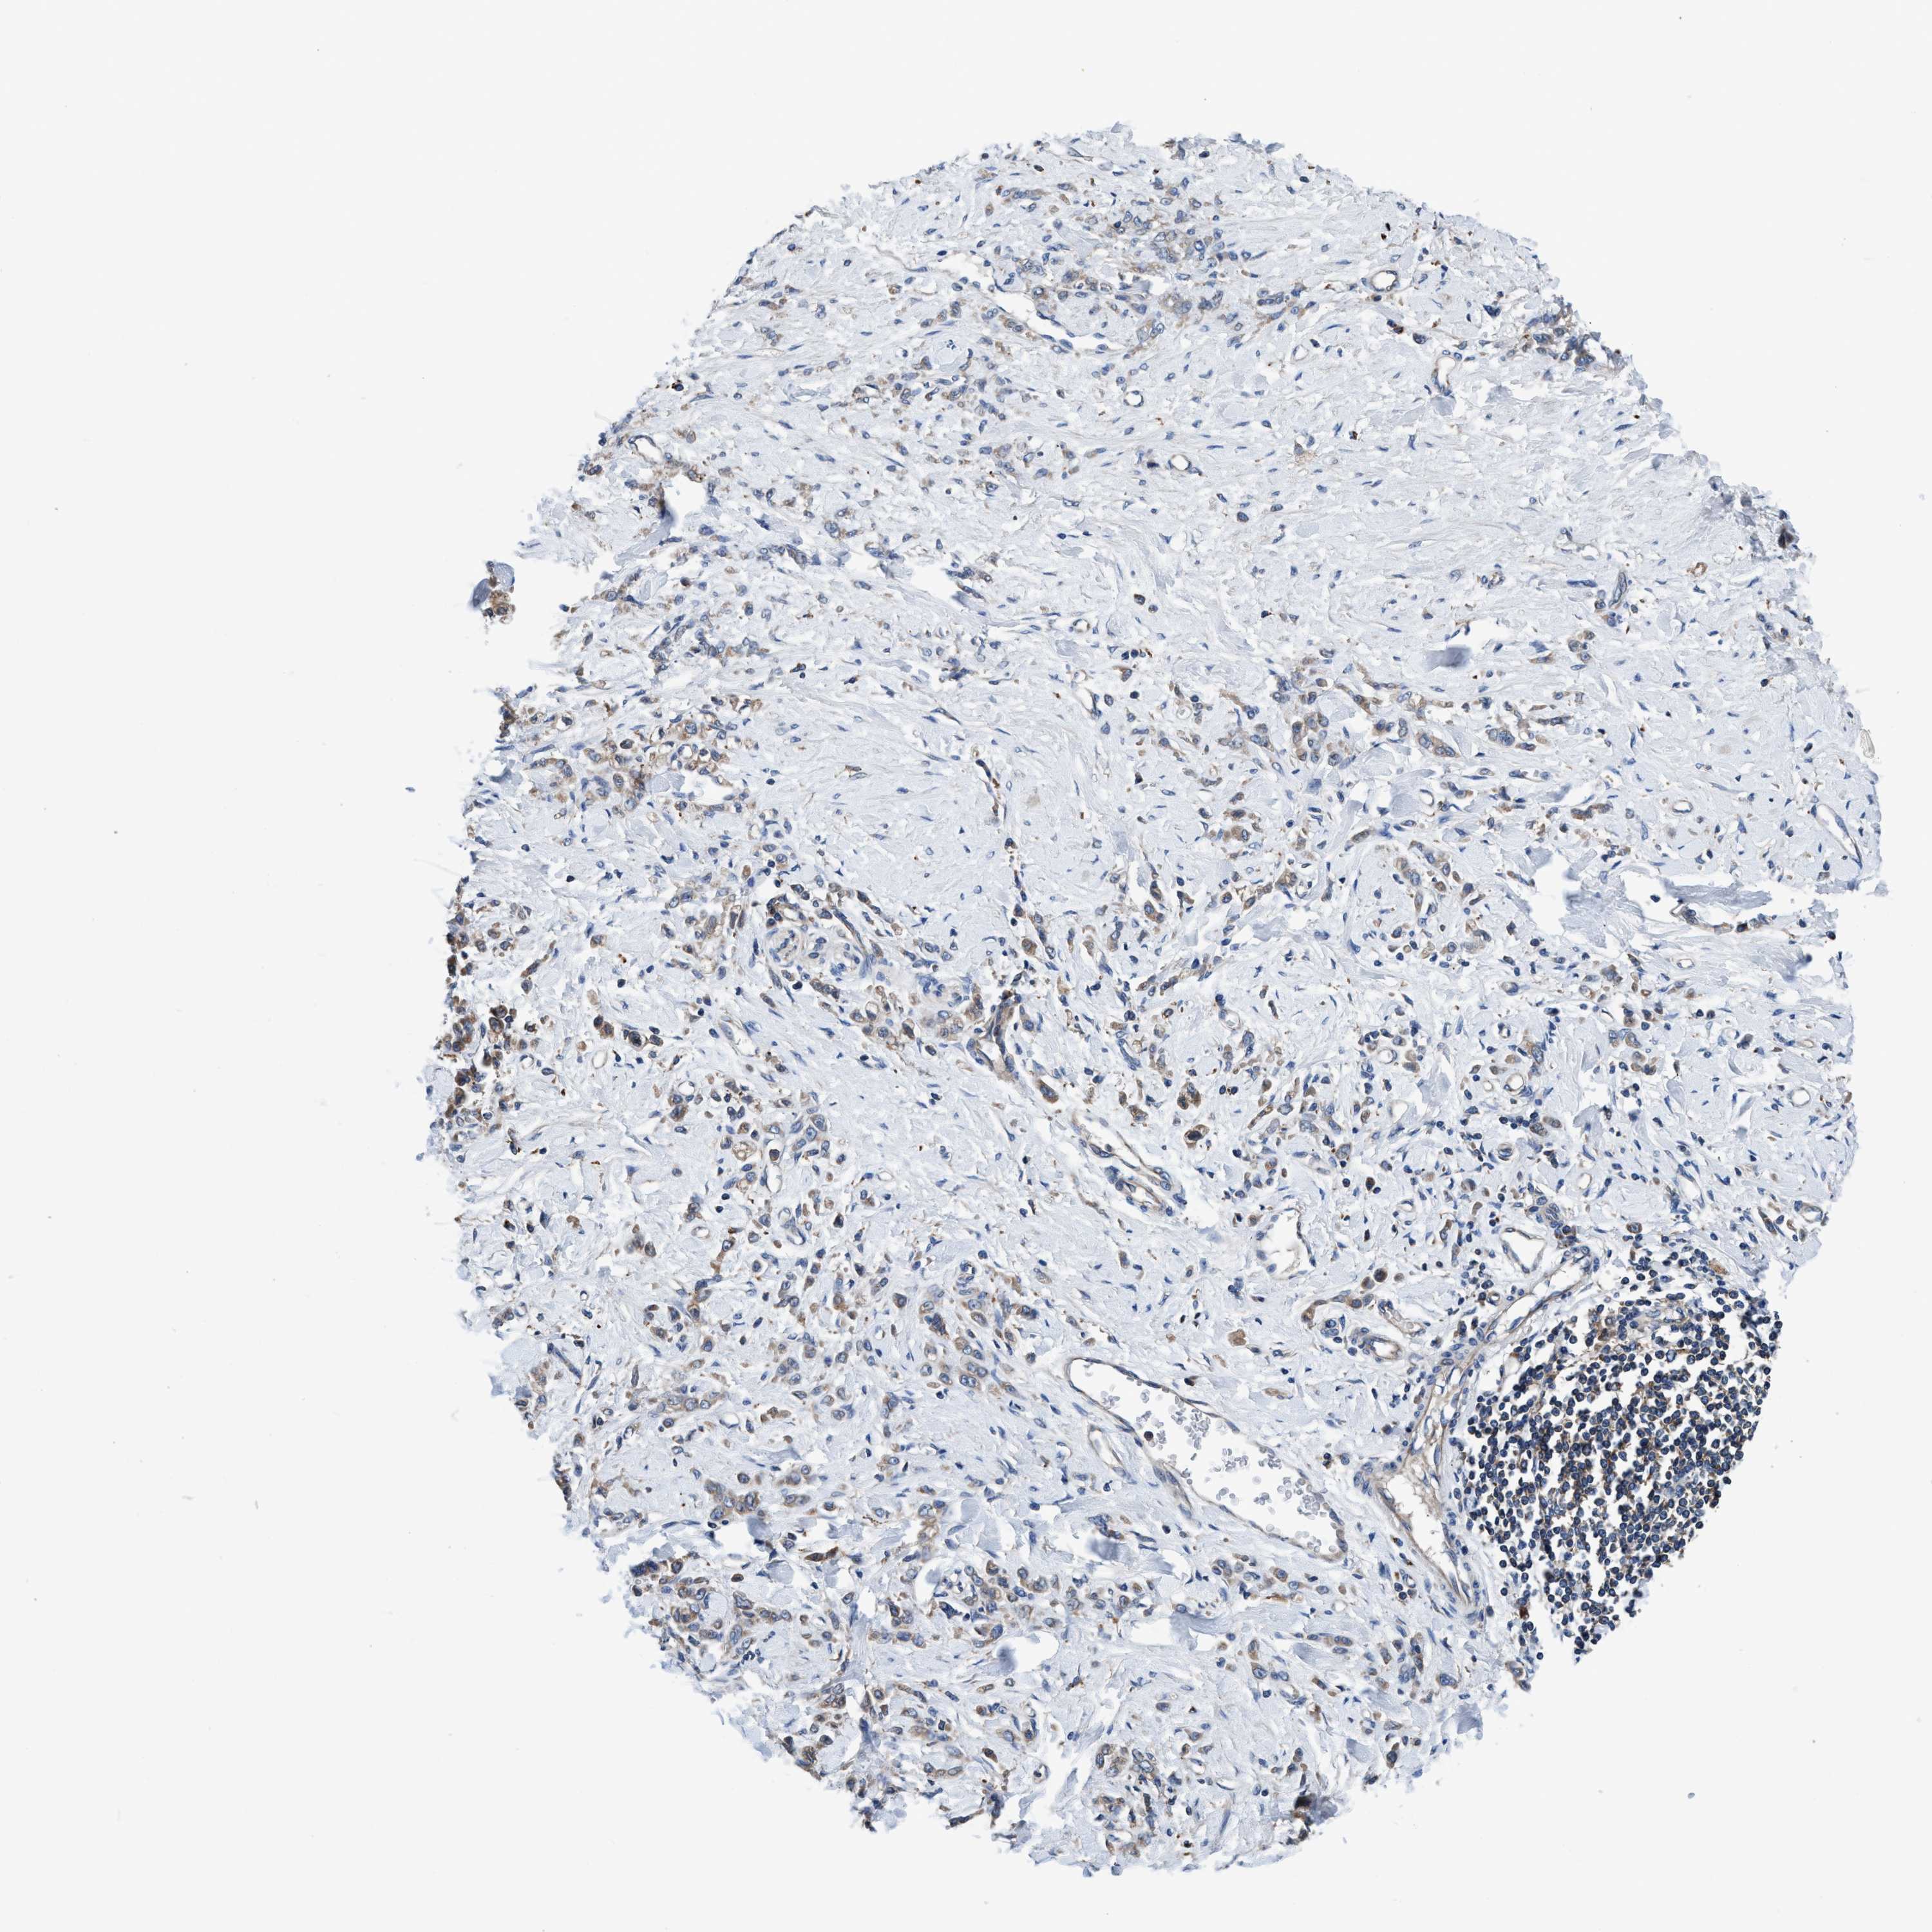

STOMACH CANCER - Protein expressioni

A mouse-over function shows sample information and annotation data. Click on an image to view it in a full screen mode. Samples can be filtered based on level of antibody staining by selecting one or several of the following categories: high, medium, low and not detected. The assay and annotation is described here.

Note that samples used for immunohistochemistry by the Human Protein Atlas do not correspond to samples in the TCGA dataset.

Antibody stainingi

Antibody staining in the annotated cell types in the current human tissue is reported as not detected, low, medium, or high, based on conventional immunohistochemistry profiling in selected tissues. This score is based on the combination of the staining intensity and fraction of stained cells.

Each image is clickable and will lead to virtual microscopy that enables deeper exploration of all samples and also displays staining intensity scores, fraction scores and subcellular localization as well as patient and tissue information for each sample.

Antibody HPA021335

Antibody HPA021830

Staining

High

Medium

Low

Not detected

Intensity

Strong

Moderate

Weak

Negative

Quantity

>75%

75%-25%

<25%

None

Location

Nuclear

Cytoplasmic/membranous

Cytoplasmic/membranous,nuclear

Adenocarcinoma, NOS